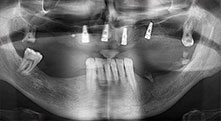

For what indications do you use the saws?

Bratu: We routinely use the instruments for harvesting bone blocks and splitting alveolar ridges. We also use the Piezomed B6/B7 for osteotomy of impacted teeth and removing failed implants. All indications that require deep, clean cuts.

Bratu: We like to use the sandwich technique for augmentation in the lateral mandible. A bone cover is prepared with the piezo saw and the crestal fragment is fixed with microscrews. We place a mixture of autologous bone and xenogenic bone replacement material in between. This works very reliably. You should always ensure sufficiently dimensioned vertical cuts when splitting the alveolar ridge in the mandible. Otherwise the bone may fracture easily.

Bratu: I consider piezo surgery a great leap forward in oral surgery. The technique makes bone preparation safer and easier. Little bone is lost, for example in extractions. This is very important in the aesthetic zone, particularly if immediate implantation is planned. Piezo surgery is also safer for soft tissue: injuries to membranes in the sinus are basically history, as are nerve injuries when bone blocks are being harvested. Data indicating reduced postoperative swelling and pain are also available. Piezo surgery is also ideal for preparation of sinus septa. And last but not least, our patients benefit from the atraumatic nature of this technology.